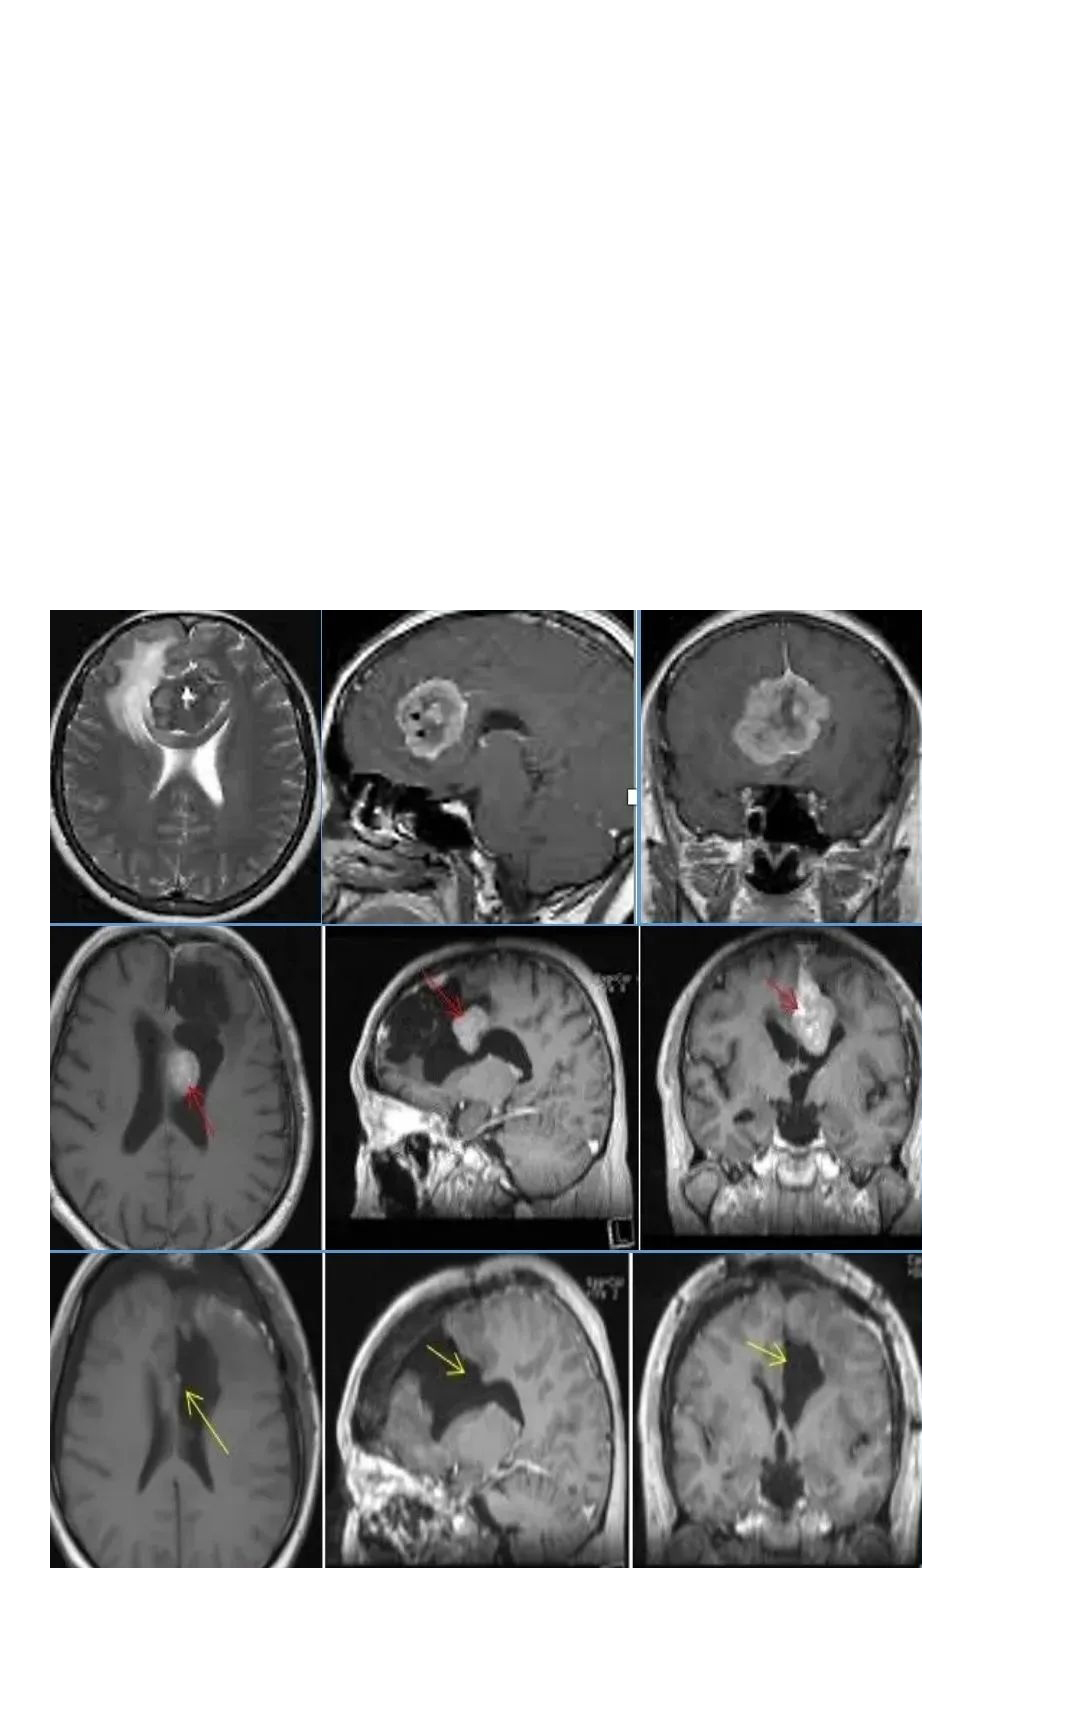

然而仅在部分切除手术的二年,赵先生就在复查检查种发现了脑膜瘤复发的情况,手术风险依旧存在,医生建议赵先生进行伽马刀治疗。3年伽马刀治疗非但没有如预期的控制肿瘤生长的效果,反而让赵先生的脑膜瘤继续恶化,MRI影像显示大脑镰前段基本均受累,并有大脑镰右侧肿瘤生长,矢状窦被累及,左侧额部凸面硬脑膜多处肿瘤生长。

术前情况:2005年,75岁的法国女士Chloe因右侧海绵窦脑膜瘤进行了一次开颅手术。2016年,她发现自己左侧视力进行性下降,检查视力结果左侧视力4.6(右侧5.0),左侧视神经管内侧病变均匀增强,还报告翼点空化是由颞肌萎缩引起的。诊断确定脑膜瘤位于视神经管的中下侧(图1),导致了视力严重恶化。

图1:术前MRI